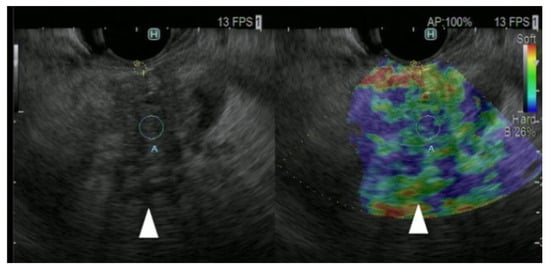

(D)

Strain elastography

Seventy-seven PCs, 42 inflammatory masses, and 10 NENs were classified into categories using the homogeneity of the color map (homogeneous or heterogeneous) and the combination of the dominant color within a color map (blue or green). They defined the combination of blue and heterogeneous as PC (Figure 5), green and heterogeneous as a benign inflammatory mass, and blue and homogeneous as a NEN. The diagnostic ability for malignant pancreatic solid lesions was 100% in sensitivity and 85.5% in specificity, respectively [26]. In a meta-analysis of 1687 patients, the diagnostic capabilities of qualitative EUS and quantitative EUS elastography for malignant pancreatic lesions were 0.98 and 0.95 in sensitivity and 0.63 and 0.61 in specificity, respectively [27]. Therefore, EUS strain elastography is an important tool for PC.

Figure 5. EUS strain elastography images of pancreatic cancer. Pancreatic lesion was detected as a low echoic lesion (arrowhead) on conventional EUS (left). EUS strain elastography detected a pancreatic lesion with a heterogeneous blue pattern (arrowhead) compared with that of surrounding pancreatic tissue (right).